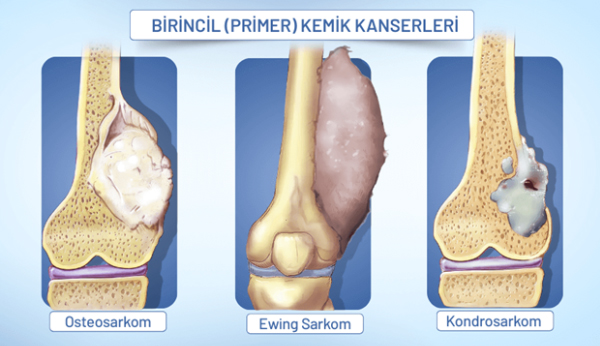

سرطان اولیه استخوان

سرطان اولیه استخوان از یک تومور بدخیم ناشی میشود که مستقیماً در سلولهای استخوانی تشکیل میشود. در حالی که علت آن اغلب ناشناخته است، میتواند با اختلالات ژنتیکی نادر مانند سندرم لی-فرامنی و اختلالات استخوانی مانند بیماری پاژه مرتبط باشد. شایعترین انواع عبارتند از:

- استئوسارکوم، که بیشتر در جوانان شایع است و از سلولهای تشکیلدهنده استخوان شروع میشود؛

- کندروسارکوم، که بیشتر در بزرگسالان مسنتر شایع است و از سلولهای غضروفی منشأ میگیرد؛

- سارکوم یوئینگ، که معمولاً در کودکان و بزرگسالان جوان رخ میدهد و میتواند هر استخوانی یا بافت نرم اطراف آن را تحت تأثیر قرار دهد.

نکته مهم این است که درد استخوان ناشی از بدخیمی به صورت درد مداوم استخوان است و با گذشت زمان بدتر میشود.